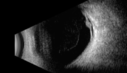

Ocular Lymphoma - non-Hodgkins - B-Cell - OCT shows multifocal sub-RPE masses 437 viewsMultifocal sub-RPE lesions in the left eye of a patient with history of Non-hodgkins B-cell Lymphoma last active 2 years agoMar 09, 2017

Ocular Lymphoma - non-Hodgkins - B-Cell - OCT shows multifocal sub-RPE masses 508 viewsMultifocal sub-RPE lesions in the left eye of a patient with history of Non-hodgkins B-cell Lymphoma last active 2 years agoMar 09, 2017